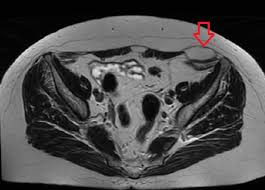

Can a ct scan miss a hernia. Most abdominal hernias can be diagnosed on the basis of findings on physical examination or plain films and barium studies. The study found that 25 percent of CT scans and 41 percent of MRI scans accurately diagnosed palpable inguinal hernias. However diagnostic dilemmas can arise when patients are obese or have had surgery.

Having done quite a lot of research I understand that its possible for the CT scan to miss the hernia as youre lying down at the time its done could this be whats happened or what else could it be. Palpable inguinal hernias were a little easier to detect but the number of misdiagnoses was still high. Yes it can not show on a CT scan and it can also be the doctors reading it overlook a small one.